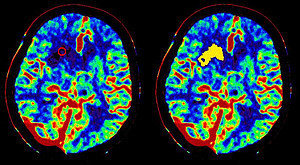

Automatic core and penumbra segmentation of stroke lesions from CT perfusion investigations